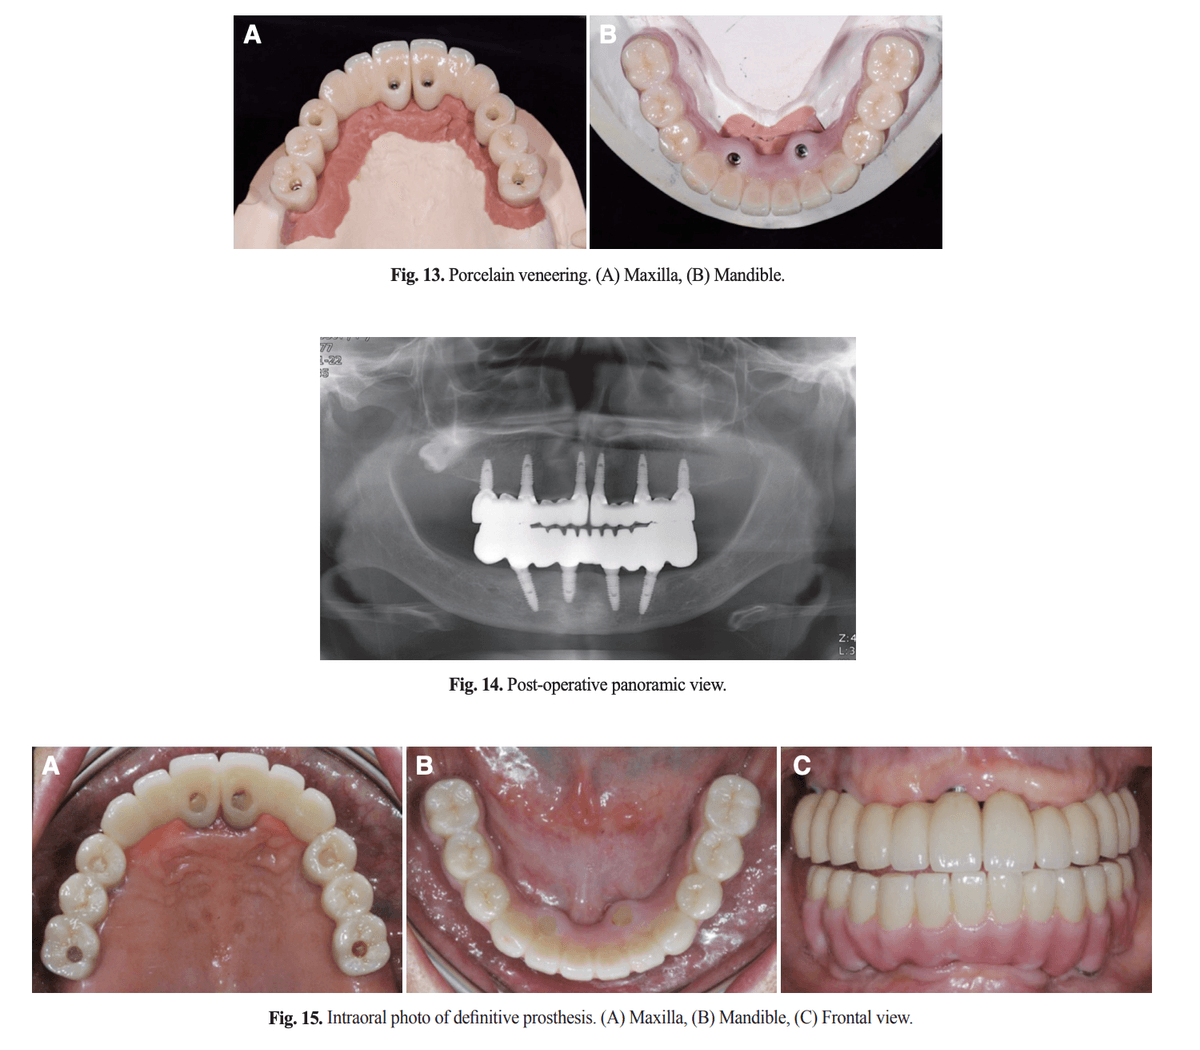

전치부 도재 축성, 장착 후 파노라마, 최종 보철물 구강 내 사진

[그림 4] 전치부 도재 축성이 완료된 상·하악 보철물(위), 장착 후 파노라마(가운데), 구강 내 장착 직후 사진(아래).

• Shortened Dental Arch 개념 — 제1대구치까지만 수복해 구치부 교합력 분산과 위생 관리를 동시에 확보했습니다.

• 견치유도 교합(Canine Guidance) — 측방 운동 시 견치만 접촉하게 해 구치부 보철에 걸리는 측방력을 최소화했습니다. 임플란트 보철의 기계적 합병증(나사 풀림·도재 파절) 예방의 핵심 원칙입니다.

• 지르코니아 프레임 + 전치부 도재 축성 — 강도가 필요한 구치부는 지르코니아 단일 구조, 심미가 필요한 전치부는 도재 비니어로 완성했습니다. 프레임은 왁스업을 스캔하는 방식으로 제작해 측방운동 접촉점을 정밀 재현했습니다.

⚠️ 전악 수복에서 가장 흔한 장기 합병증은 도재 치핑(porcelain chipping)입니다(Goodacre 2003). 이를 줄이려면 ① 견치유도 등 보호 교합 설계, ② 측방·전방 접촉점 제어, ③ 주기적인 교합 재조정이 필수입니다.

참고 증례(Shin & Paek, JKAP 2019)에서는 보철 장착 이후 5년간 도재 치핑이나 임플란트 주위염 같은 합병증 없이 변연골과 보철이 안정적으로 유지되었다고 보고되었습니다. 이런 결과가 나오기까지는 네 가지 요인이 복합적으로 작용했습니다.